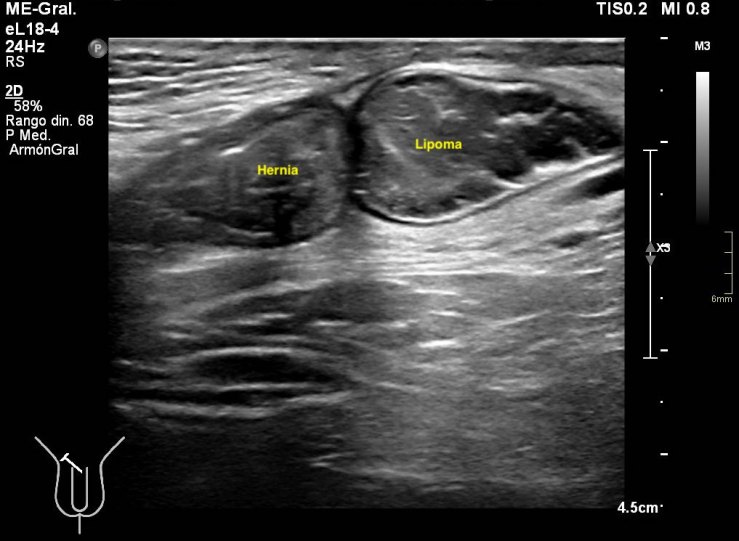

291. Lipoma de cordón y hernia inguinal.

En algunas ocasiones te encuentras cosas muy chulas, sin esperarlas, son esas cosas que no olvidas. Esta semana entró en la sala un paciente para descartar una hernia inguinal, valorada por el cirujano previa a la cirugía. Cuando el paciente se tumbó en la camilla y se descubrió la región inguinal, era evidente que algo pasaba porque tenía un bulto muy llamativo, duro. Justo cuando le puse el traductor y sin tiempo para reaccionar la hernia se corrigió, el bulto desapareció…casi. Me di cuenta que la hernia existía, sin verla, así que me pude a evaluar la región inguinal desde le teste, buscando el canal inguinal…Sorpresa…

Nada más acabar el testículo y empezar el canal inguinal me encontré una estructura hipoecogénica, con septos, con un borde ecogénico a modo de cápsula muy llamativo. La estructura era dura y fija, no respondía a valsalva, enseguida me dí cuenta de que no era parte de una hernia, no era una tripa, porque no se movía…siguiente sorpresa…

Cuando le pedía al paciente que hiciera valsalva, y por el canal inguinal aparecía una hernia muy evidente, con un cuello visible en dos proyecciones, la hernia tenía tanto grasa como asas intestinales, sonaba al entrar y al salir.

Lo más llamativo y lo que más me gustó de la prueba es que cuando la hernia llegaba a la estructura fija que estudié en primera instancia, la abrazaba, se apoyaba en ella y o conseguía moverla…y después retrocedía introduciéndose en la cavidad abdominal.

La hernia era una hernia más, el bultoma me hizo saltar las alarmas y se lo comuniqué al radiólogo responsable. Ante la sospecha razonable de que pudiera ser un tumor, decidió ampliar con un TAC de Pelvis sin CIV que demostró la existencia tumonal benigna que correspondía con un lipoma de cordón, benigno, por su aspecto amable, bordes definidos, tabique externo y centro graso.

Hernia inguinal, con foramen de 15 mm, con introduccion en saco herniario de 3 cms, de grasa omental. Imagen nodular en cordon, distal, de 2 cms, que sugiere patologia benigna.

En una misma región coexistiendo dos figuras patológicas. Fue muy bonito ver que la hernia tocaba el lipoma y retrocedía, disfruté comprobando que los hallazgos ecográficos se confirmaron con el scanner. El caso es precioso y quería que lo vieses, y en esta noche lluviosa y fría, te lo dejo en imágenes…Espero que te guste.

De la imagen 2 a la 5 puedes ver documentado y medido en dos planos con doppler la lesión fija en el cordón.

De la imagem 6 a 8 puedes ver la lesión y su relación con la hernia, en la 6, no se ve la hernia, pero sí el canal inguinal, en la 7 y la 8 observas como la hernia toca el lipoma casi abrazándolo.

La 9 demuestra el contenido de tripas en la hernia.

La 10 y la 11 como la hernia se retira paulatinamente cuando el paciente deja de hacer la maniobra de valsalva.

La imagen 12, lo que corroboraba la sospecha de lesión tumoral en el cordón a expensas de la coexistencia de una hernia en esa localización. Precioso, TODO.